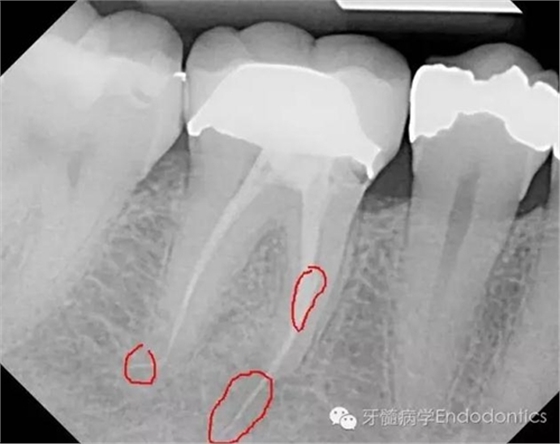

患者因右下第一前磨牙劇烈疼痛、腫脹來診,自訴2年前該牙行根管治療,突發(fā)劇痛。X線示患牙已行根管治療并超填?;佳涝\斷為已行根管治療合并急性根尖周膿腫。一些牙醫(yī)和牙髓病??瓶赡軙?huì)直接采取根尖手術(shù)治療患牙,而我認(rèn)為手術(shù)是最終手段,尤其對(duì)于該病例。

圖2.術(shù)前X線片(b)